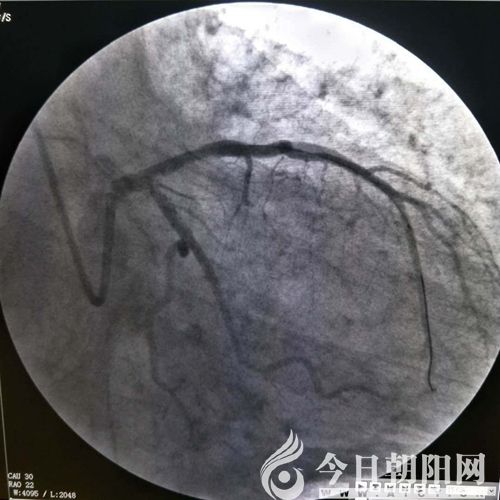

鄭某術(shù)前

兩名患者均屬于危急情況,相比之下,患者鄭某更重一些。單爽立即為鄭某實(shí)施手術(shù),術(shù)中見(jiàn)冠脈前降支支架內(nèi)100%狹窄,回旋支80%狹窄,血管內(nèi)布滿(mǎn)新發(fā)血栓,操作難度非常大。在導(dǎo)絲和球囊艱難通過(guò)后,依次進(jìn)行預(yù)擴(kuò)球囊及后擴(kuò)球囊于支架內(nèi)擴(kuò)張,前降支恢復(fù)三級(jí)血流,患者癥狀立即緩解。由于120急救中心在接診患者過(guò)程中,及時(shí)予以診斷,并開(kāi)通綠色通道、免費(fèi)心梗“一包藥”口服、建立左手靜脈通路等及時(shí)正確的處置,為患者的救治贏(yíng)得了時(shí)間。